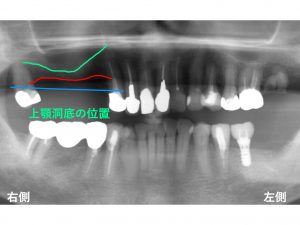

今回のケースでは、骨吸収が大きく起こっていました。

まず、本来の骨の位置を青線で記入します。

現在の骨の位置は、赤線です。

骨が吸収してしまったのです。

もう一つ問題となるのがさらに上方にある

上顎洞という部位です。

以下の緑線です。

この上顎洞は、空洞なのです。

もし、骨吸収がする前の青線まで骨があった場合には、

以下のようにインプラント治療を行います。

しかし、現在は、骨吸収がありますから

このままでは、以下のように短いインプラントしかできません。

そこで特殊な方法をとり

少しでも長いインプラントを埋入する方法を考えます。

ソケットリフト法と言われる方法です。

これは上顎洞の中に人骨の骨を入れて、

高さを増大させる方法です。

こうすることで少しでも長いインプラントを行うことが可能になります。

次に手前の欠損部分です。

奥歯よりは、骨の高さは確保されていますが、

それでも十分な長さとは言えません。

短いインプラントとなってしまいます。

そこで上顎洞に沿わせながら

少しでも長いインプラントを埋入する方法を行うことにしました。

インプラントの傾斜埋入です。

多少の傾斜であれば、問題ありませんし、

十分効果が発揮できます。

以下が先日行いました治療後です。